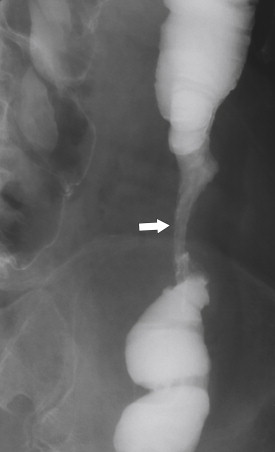

Figure 5-36, BE in a 71-year-old man with a left mid-descending colon stricture ( arrow ) secondary to fibrosis from prior ischemic colitis.